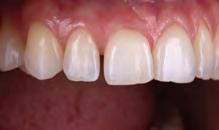

A 31-year-old woman presented with cosmetic concerns regarding her smile and requested a conservative enhancement. After clinical and radiographic analysis, digital 35mm photographs were taken and reviewed by the restorative clinician, technician, and surgeon (Fig 1). A digital impression was taken of the maxillary and mandibular arches using an intraoral scanner (Trios 3, 3Shape; Fig 2), and a smile design was developed with NemoSmile Design 3D software (Nemotec; Fig 3a). This allows for a facially driven smile frame to be created using reference lines of facial and smile proportions and natural teeth shapes and textures from the digital library (Fig 3b).

After developing the simulated mock-up, a 3D-printed resin model was created using CAD software (Fig 4a), and a clear PVS matrix (Exaclear, GC America) was fabricated to replicate the printed diagnostic wax-up using a nonperforated tray (Fig

Fig 1 Preoperative clinical views of a 31-year-old woman presenting with diastemas and limited tooth visibility. (top) Portrait. (center row) Intraoral views. (bottom row) Smile.

4b). This matrix was used to create an intraoral motivational mock-up with bis-acryl composite (Luxatemp Ultra, DMG). This additive mock-up provides the interdisciplinary team with an intraoral translation for evaluation (Fig 5). Upon evaluation of the digital smile frame and the clinical translation, it was determined that multiple esthetic and restorative requirements were necessary for an optimal biologic framework, and the interdisciplinary team determined the best sequence for these procedures. The patient was presented with the interdisciplinary treatment possibilities that included restoring the maxillary anterior teeth and premolars with a minimally

invasive preparationless procedure or with less conservative veneer preparations. The restorative materials discussed included injectable resin composites and ceramic (ie, feldspathic, pressable, machinable). For an optimal biologic framework and health, it was determined that connective tissue grafting would be necessary for treatment of the recessiontype defects on the maxillary left central and lateral incisors, canine, and premolars. The patient opted for the conservative preparationless composite veneers using the injectable resin technique followed by a connective tissue surgical procedure using the tunneling technique.